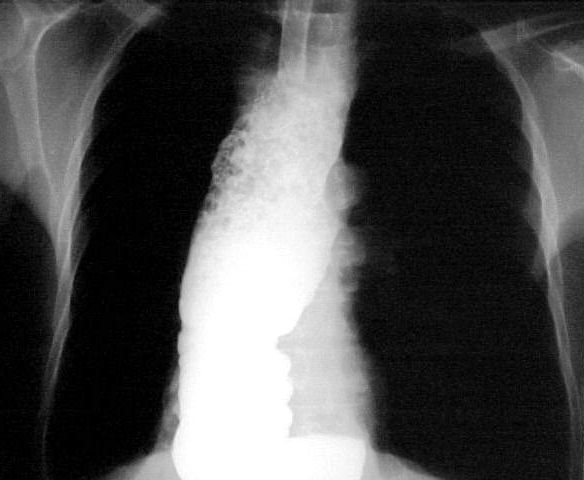

На протяжении второй стадии паразиты концентрируются, в основном, в сердце или мускулатуре пищеварительного тракта. До 30% пациентов страдает от нарушений сердечной деятельности и до 10% – от изменений в органах пищеварения (характерна гипертрофия пищевода или толстой кишки), нервной системе или целом ряде органов. В последующие годы инфекция может приводить к внезапной смерти или сердечной недостаточности, вызываемой прогрессивным разрушением сердечной мышцы.